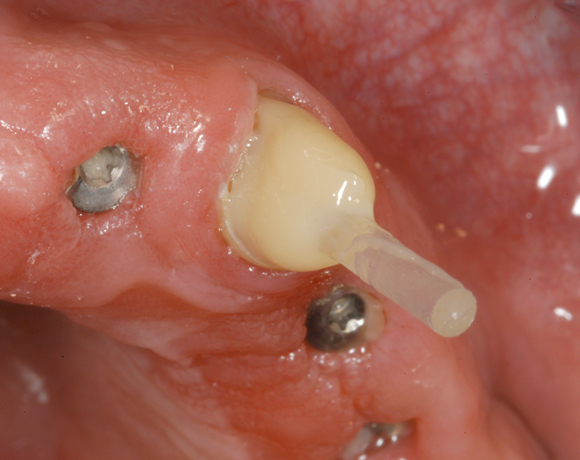

Im nachfolgenden Patientenfall wird ein Zahn mit einem Stift soweit aufgebaut, dass es möglich wird ihn wieder mit einer Krone zu versorgen.